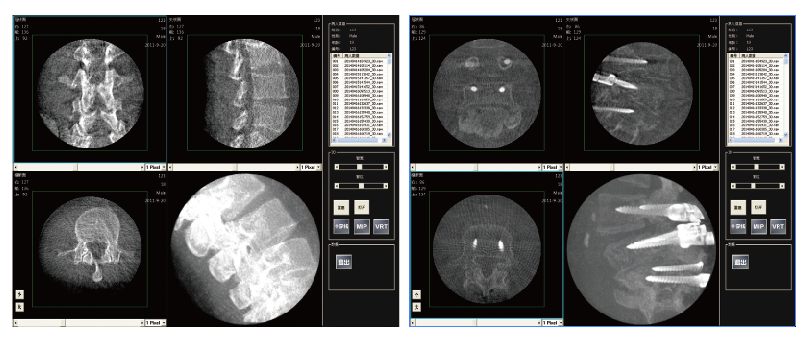

PLX7200三維C形臂骨科手術(shù)應(yīng)用

2、植入物位置更加準確,確保手術(shù)安全,提高手術(shù)的效果。

3、通過一次多角度自動采集,既可獲得全面、準確的影像信息,減少重復(fù)采strdfgwgl集次數(shù),投照劑量和手術(shù)時間也相應(yīng)減少。

4、在手術(shù)結(jié)束之前使用,在手術(shù)室既可以完成三維評估,準確地檢測定位誤差并及時進行修正,不再需要術(shù)后移至CT室進行復(fù)查,減少因錯位等原因進行二次手術(shù)的可能。